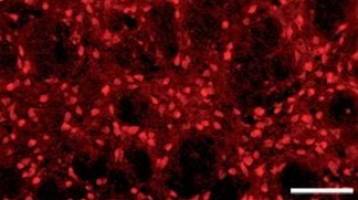

Mimicking Phosphorylation at Serine 87 Inhibits the Aggregation of Human α-Synuclein and Protects against Its Toxicity in a Rat Model of Parkinson's Disease. Several lines of evidence suggest that phosphorylation of α-synuclein (α-syn) at S87 or S129 may play an important role in regulating its aggregation, fibrillogenesis, Lewy body formation, and neurotoxicity in vivo.